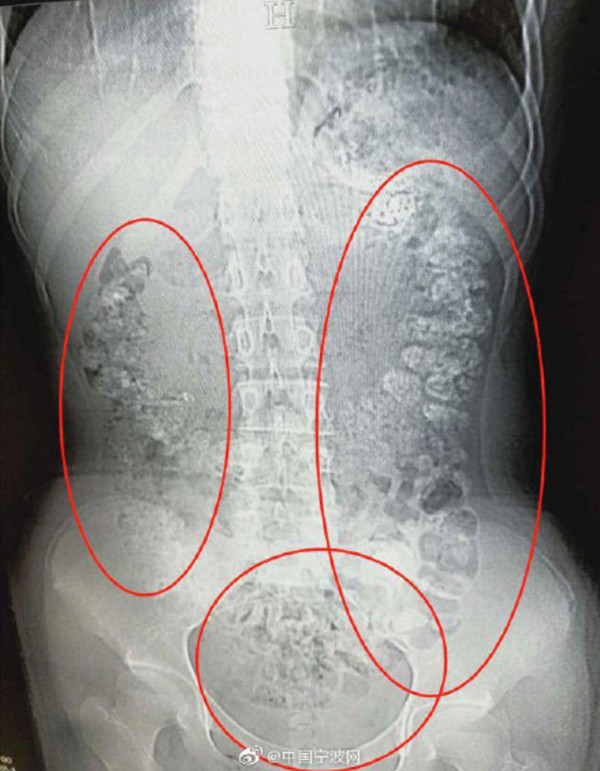

Sau khi đưa bé đi chụp CT, bác sĩ cũng phải hốt hoảng khi nhìn kết quả chụp chiếu thấy hàng trăm hạt trân châu kẹt trong bụng bé gái 14 tuổi mê trà sữa.

Có rất nhiều quả bóng hình cầu nhỏ chen chúc bất thường trong bụng bé gái 14 tuổi. Bác sĩ kết luận đây chính là các hạt trân châu trong trà sữa - một loại đồ uống đang rất được giới trẻ yêu thích.

| Ảnh chụp cho thấy có rất nhiều hạt trân châu bị kẹt trong bụng bé gái 14 tuổi. |